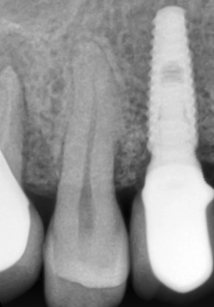

Majoritatea coroanelor sunt fixate prin înșurubare pe platforma implantului, dar sunt și variante care se cimentează. La cele realizate prin înșurubare, coroana are un orificiu prin care aceasta se strânge cu ajutorul unei chei dinamometrice pe implant, ulterior acest orificiu acoperindu-se cu materiale compozite. După fixarea coroanei, poziționarea corectă a acesteia este verificată radiografic.(Fig. 3.5.12) Coroanele simulează forma și aspectul dinților naturali și ajută la refacerea funcției și esteticii dentare. (Fig. 3.5.13)